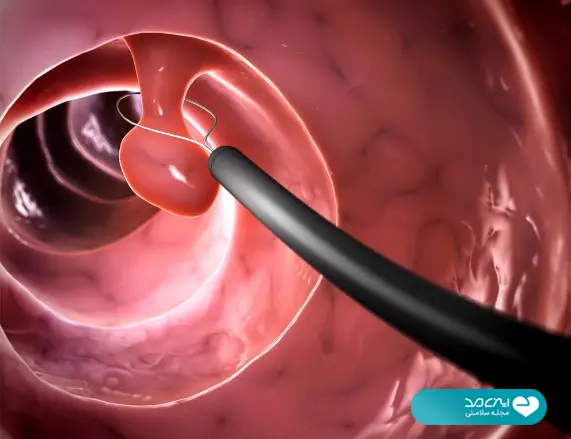

کاملترین راهنمای غربالگری سرطان روده + غربالگری رایگان آنلاین؛ بهترین زمان و روش برای تشخیص زودهنگام

تایید شده توسط پزشکان متخصص ایزی مد محتوای این مقاله صرفا برای افزایش آگاهی شماست. قبل از هرگونه اقدام با پزشکان ایزی مد مشورت کنید عنوان موضوعات این صفحه غربالگری سرطان روده بزرگ را میتوان مکملی برای روشهای پیشگیری دانست، اقدامی که شانس بروز عوارض…